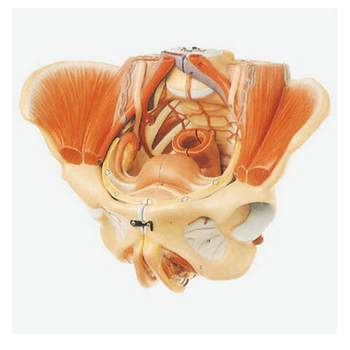

GD/A15107女性骨盆附生殖器官與血管神經模型產品介紹:1、型號規格:GD/A151052、名 稱:女性生殖器官結構模型3、品 牌:全科醫生4、簡 介:該模型由女性生殖器官正中矢狀切面、盆部...